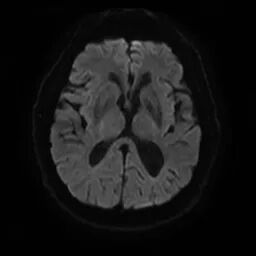

颅脑磁共振+头颈MRA:未见新发梗死;右侧颈内动脉C1段重度狭窄。